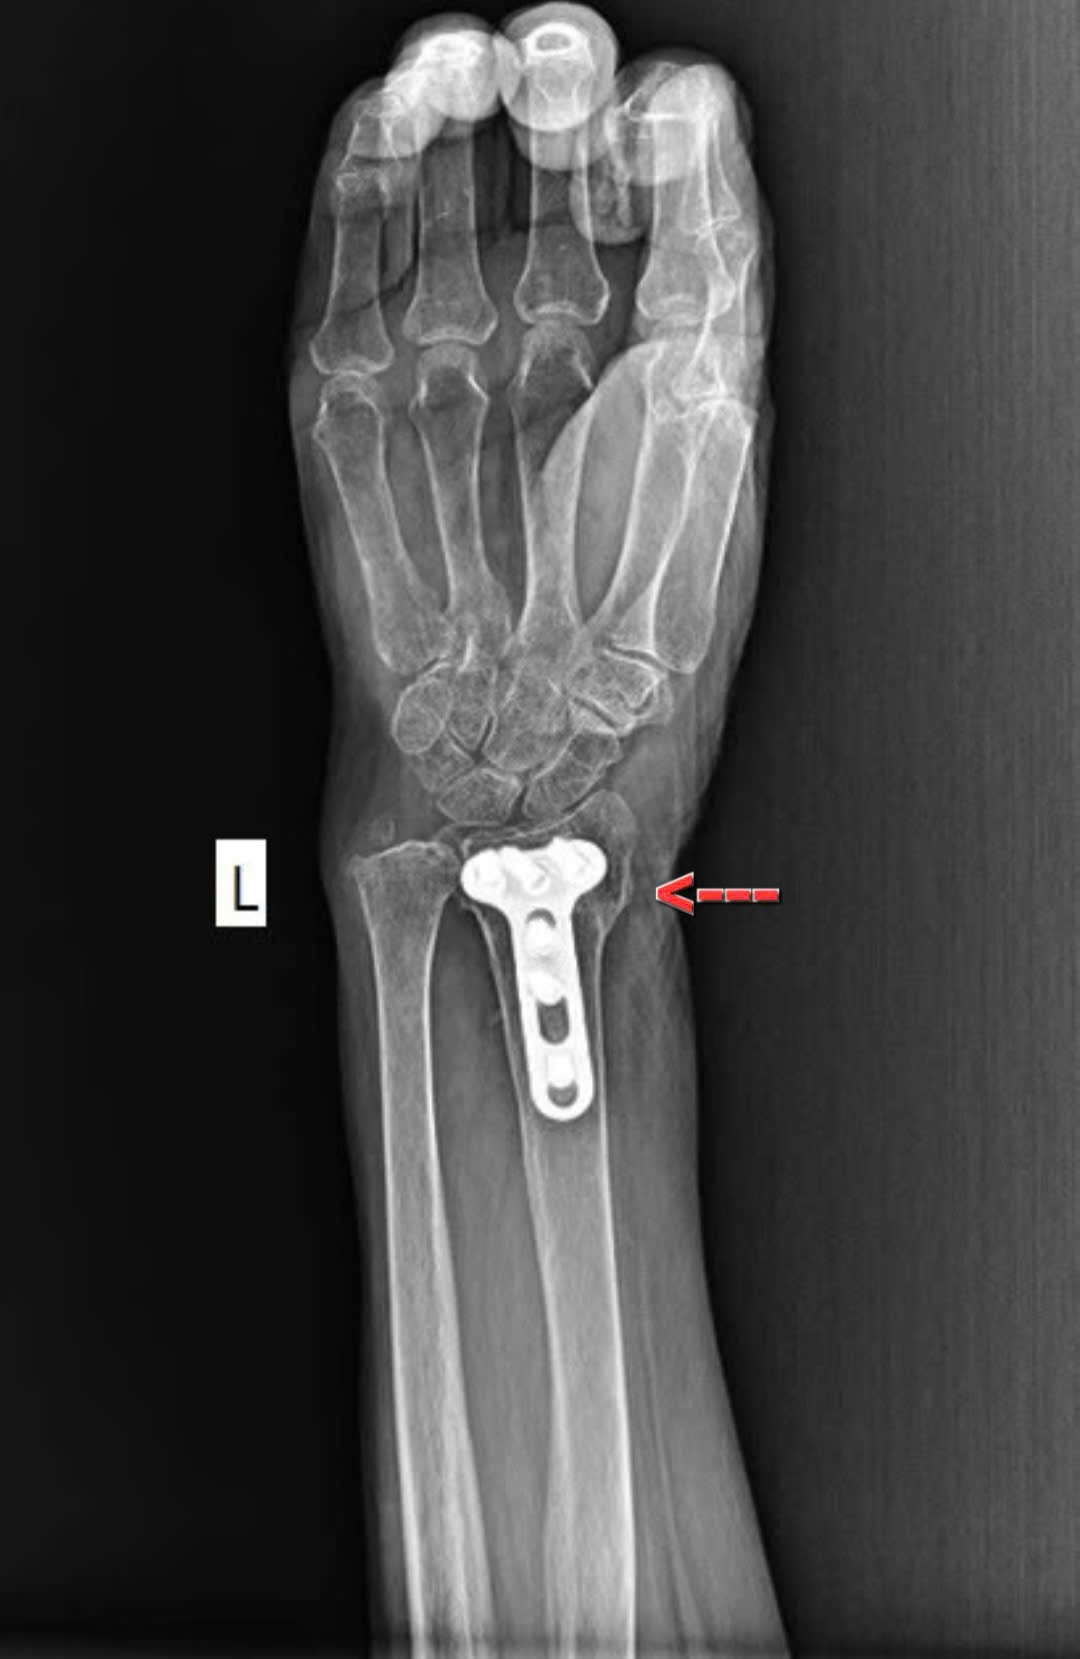

Bệnh nhân nữ 72 tuổi chẩn đoán: gãy kín đầu trên xương cánh tay trái

Kèm theo gãy kín đầu dưới xương quay trái

Được mổ và theo dõi tại Trung tâm y tế Khu vực Thuận An sau 3 tháng xương lành tốt vận động như bình thường. Đây là hình ảnh X quang sau 9 tháng xương lành rất tốt

X quang sau 9 tháng xương gãy lành rất tốt